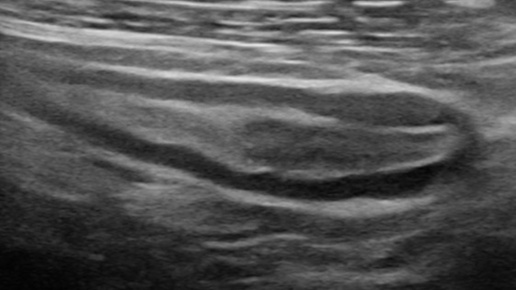

Острый аппендицит и мочекаменная болезнь (УЗИ)